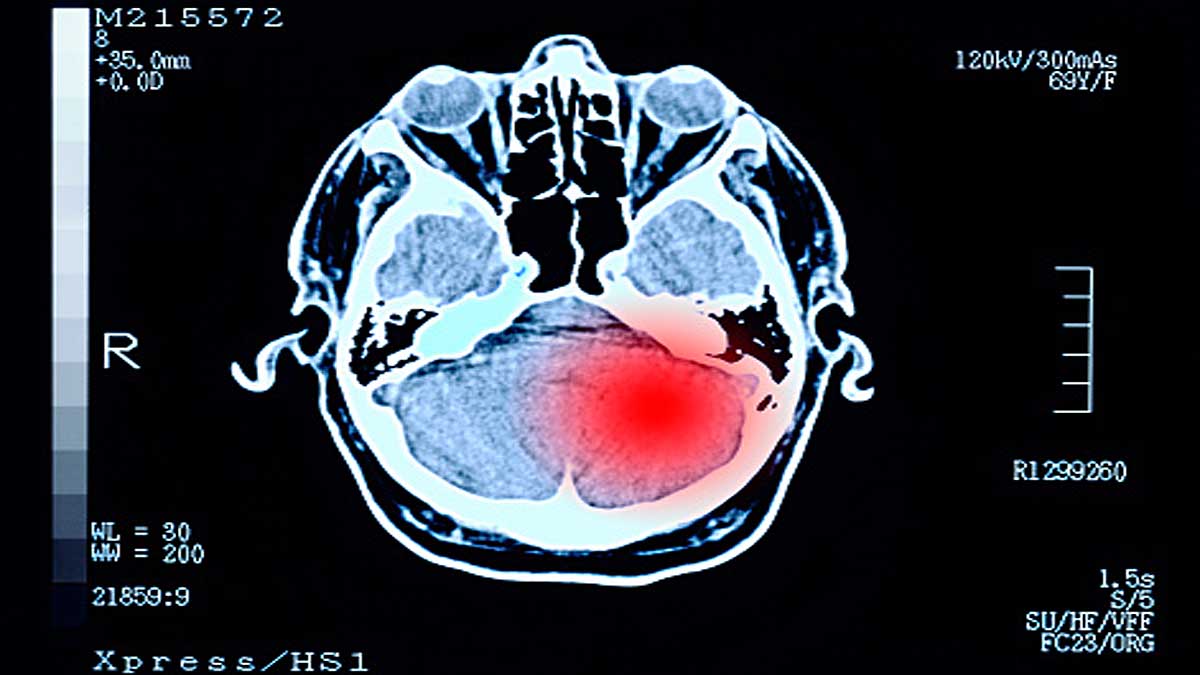

कोरोना से पीड़ित 85 फीसदी लोगों में लगातार चार तरह की दिमागी समस्याएं देखने को मिल रही हैं. ये न्यूरोलॉजिकल दिक्कतें काफी दिनों तक कोरोना पीड़ित को परेशान कर सकती हैं. इनमें शामिल हैं दिमाग में कोहरा पैदा होना, सिरदर्द, सूंघने और स्वाद को समझने की ताकत कम होना. ये उनके साथ भी हो सकता है जो कोरोना पीड़ित तो हुए लेकिन अस्पताल में भर्ती नहीं हुए या गंभीर रूप से बीमार नहीं पड़े. ये खुलासा एक नई स्टडी में हुआ है. (फोटोःगेटी)

एनल्स ऑफ क्लीनिकल एंड ट्रांसलेशनल न्यूरोलॉजी (Annals of Clinical and Translational Neurology) जर्नल में 23 मार्च को प्रकाशित इस स्टडी में अमेरिका के 21 राज्यों के 100 कोविड-19 मरीजों पर अध्ययन किया गया है. इन मरीजों का अध्ययन, इनसे बातचीत और इनकी जांच शिकागो स्थित नॉर्थवेस्टर्न मेमोरियल अस्पताल के वैज्ञानिकों ने मई 2020 से नवंबर 2020 तक की. उसके बाद इसकी रिपोर्ट बनाई गई. (फोटोःगेटी)